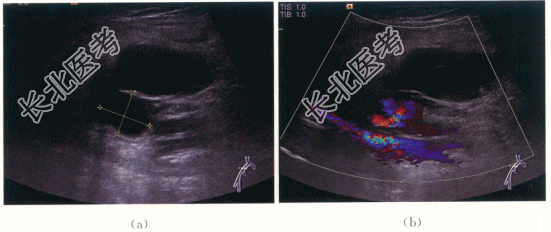

患者,女,71岁,因“发现双侧颈内动脉狭窄1年”就诊,局麻下右侧腹股沟股动脉穿刺插管行右侧颈内动脉支架置入术,术后1周出现右下肢肿胀不适,无发热。

患者神清,反应好,双瞳等大,对光(+),颈软,肢体活动好。右腹股沟穿刺点皮下硬结、皮肤青紫,右下肢肿胀,足背动脉搏动存在。

D-二聚体1.07mg/L。

- 简答题1、患者的诊断及超声依据是什么?